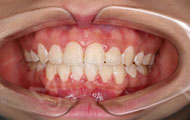

2017/04/22 矫正结束前

不说了,直接看效果吧,同样的牙套,曾经选择错误的医生让我不适应,而麦芽医生把我的脸型都整好看了,这就是差距!!别看同样的产品,不同的医生使用效果是不一样的,千万不要像我一样,更不要比价格什么的,牙套就那几款,但是下次让我第一次选择的时候我一定会先看效果再看价格,麦芽的性价比是真的高!顺便洗了个牙,我觉得我以后的牙齿问题可能都会在麦芽了,这里有一群厉害的医生,让我很放心!

幼儿园的小朋友更愿意和我亲近了,说喜欢何老师上的课,喜欢和何老师玩~~~很多人问我是不是参加了“变形记”,有的人还问我在哪里整容的,脸型怎么这么好卡性格比之前更开朗了!其实我只是牙齿参加了变形记,矫牙美脸说的就是我了,没有整容!一年前有多伤心有多苦恼,今天笑的就有多开心!未来,我会一直坚持做一名园丁,为更多的小朋友带去欢乐~~~